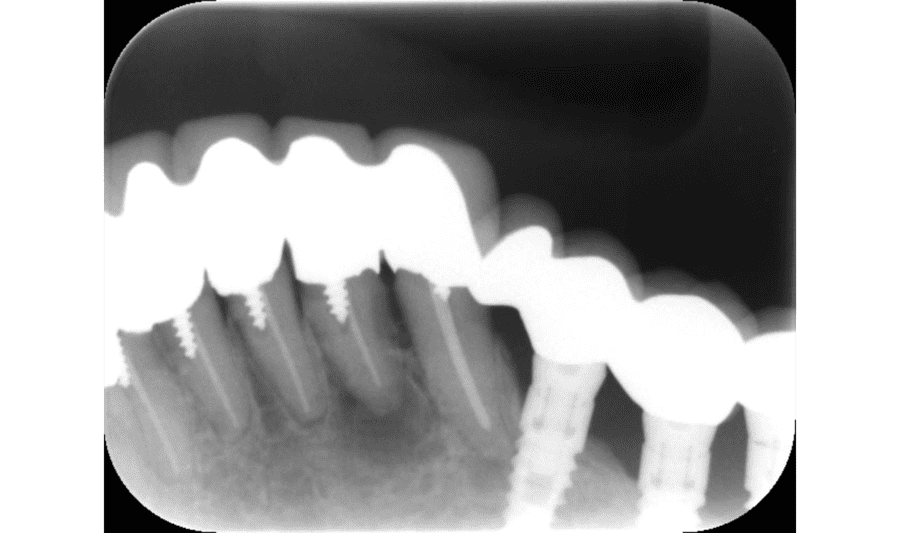

After

16か月後(さらに骨が回復している)